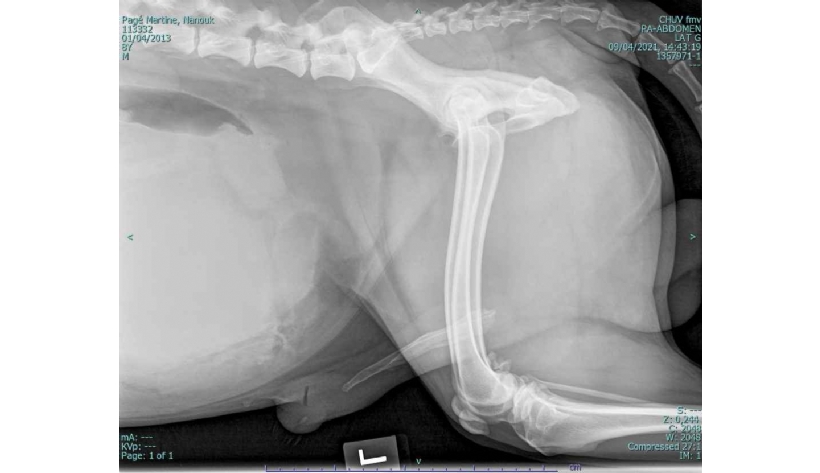

Mercredi 29 Octobre 2025 Animaux de compagniePhoto n° 1A : Radiographie abdominale latérale gauche.

Un chien husky mâle entier de 8 ans est présenté pour dysurie et strangurie évoluant depuis 5 jours. Deux jours auparavant, une numération formule ainsi qu'un examen biochimique sanguins avaient été réalisés, sans montrer d'anomalie. Un traitement symptom...